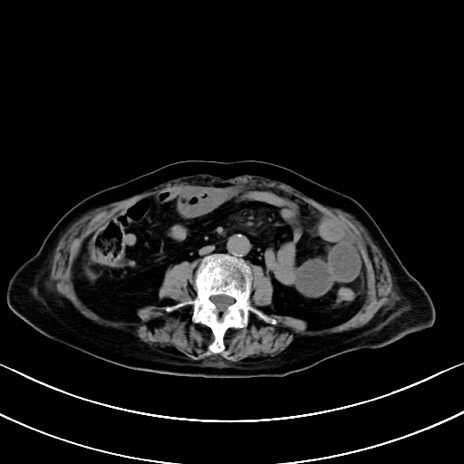

症例40(横断像)他院1日前

横断像

他院CT